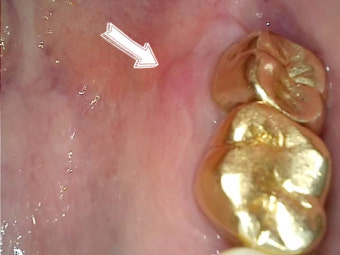

🔍 시진(눈으로 보기)

- 거울 앞에서 입을 최대한 벌리고 손전등 또는 스마트폰 불빛을 비춰보면 입천장 상태를 확인할 수 있습니다.

- 붓기, 발적(붉어짐), 흰색 반점, 궤양, 수포 등이 있는지 관찰합니다.

- 비대칭적으로 한쪽만 붓는 경우는 특히 주의해야 합니다.